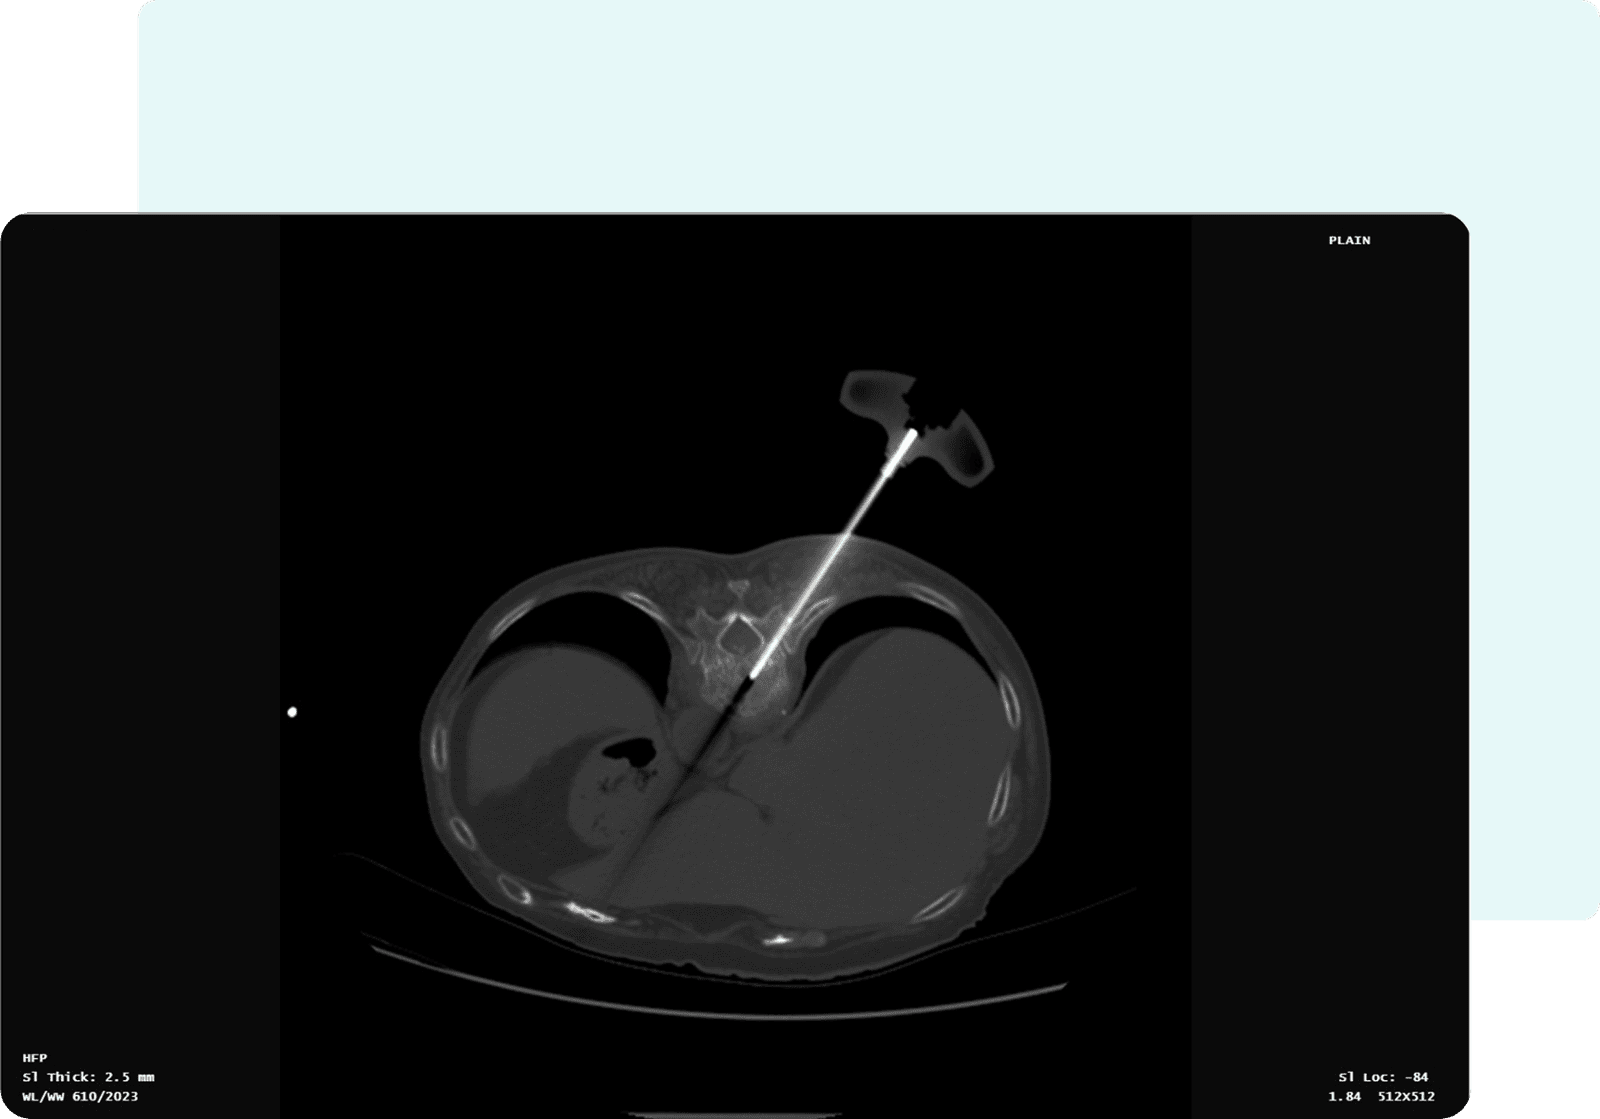

- Needle Length: 6.65 cm

- Entry Slice Number: 8

- Target Slice Number: 8

- Orbital Angle: 33.99°

- Cranio-Caudal (CC) Angle: 0°